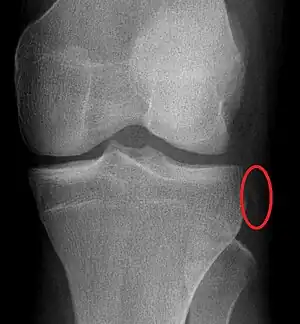

| Segond fracture of left knee | |

The Segond fracture is a type of avulsion fracture (soft tissue structures pulling off fragments of their bony attachment) from the lateral tibial plateau of the knee, immediately below the articular surface of the tibia.[1]

Segond and reverse Segond fractures are characterized by a small avulsion,[6] or "chip", fragment of characteristic size that is best seen on plain radiography in the anterior-posterior plane. The avulsed fragment of bone may be very difficult to see on the plain x-ray exam, and may be better seen on computed tomography. MRI may be useful for visualization of the associated bone marrow edema of the underlying tibial plateau on fat-saturated T2W and STIR images, as well as the associated findings of ligamentous and/or meniscal injury.